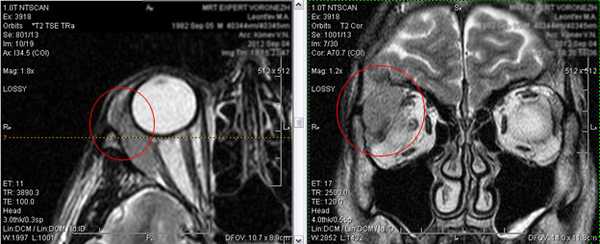

3. Миозит.

Возникновение данного заболевания, зачастую, связано с простудным фактором. Проявляется острой болью в глазах и глазницах, особенно при тех движениях глазного яблока, в которых участвуют пораженные мышцы. Далее развивается экзофтальм, диплопия.

Для более детального изучения выявляемой патологии возможно проведение внутривенного контрастирования (введения контрастного вещества):

На изображении слева-снимок без контрастного препарата, на изображении справа - с контрастированием.